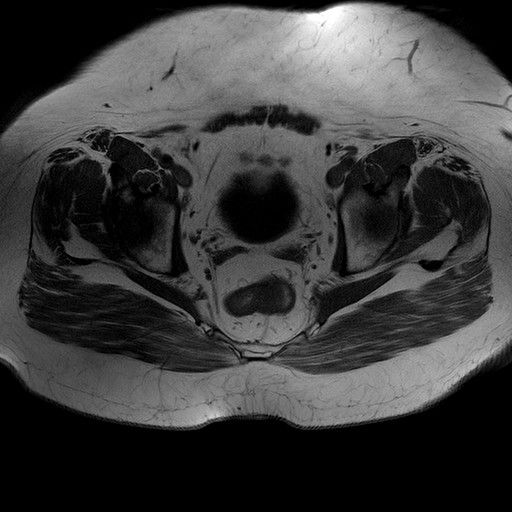

Esami: RMN BACINO

T1W_TSE

Evidenti e simmetriche alterazioni osteofitosiche in regione coxo femorale con riduzione delle rime articolari. Degenerazione completa del cercine glenoideo. Non attuali segni di versamento articolare. Non segni di edema osseo che escludono attuale algodistrofia od osteonecrosi. Lieve e simmetrica riduzione del trofismo della muscolatura glutea.